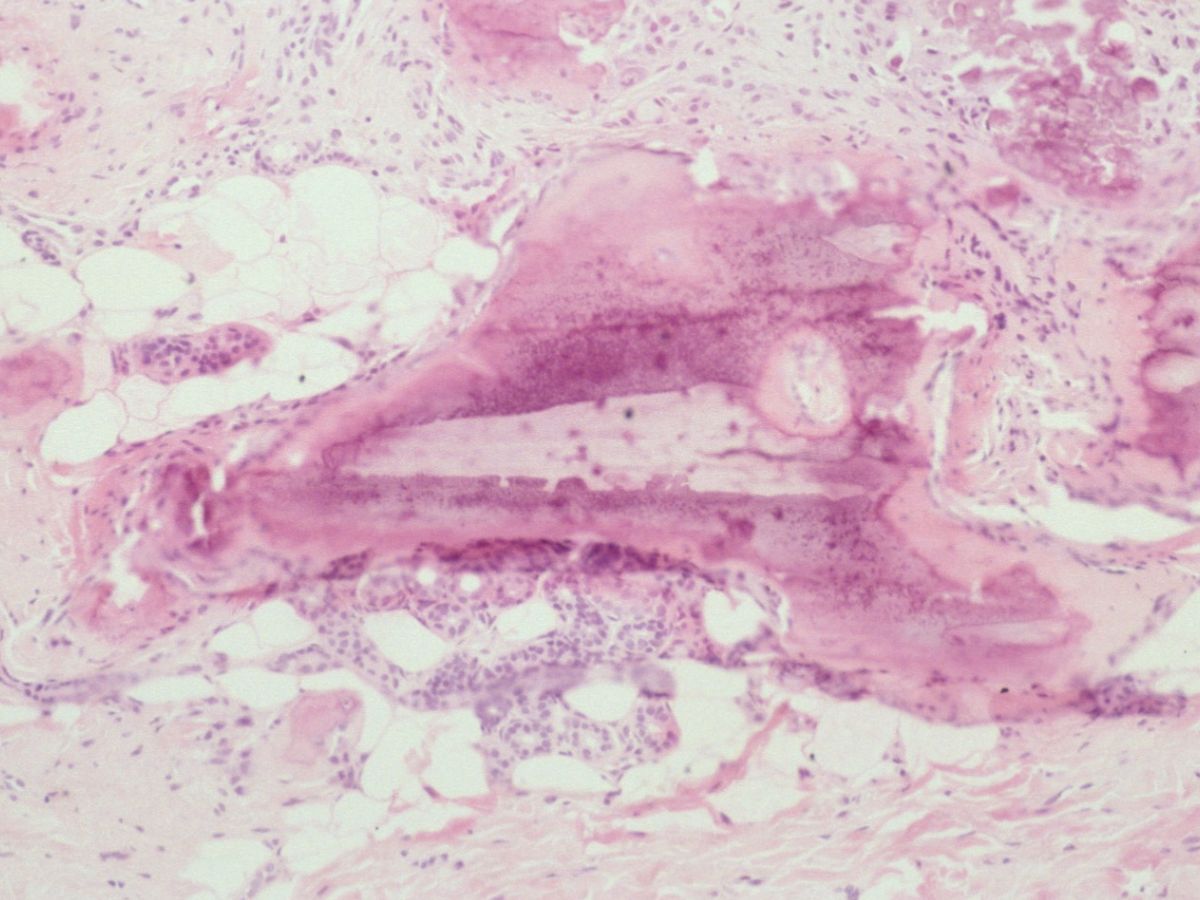

![Osteoma cutis (click on photo to enlarge) [source: www.huidziekten.nl] Osteoma cutis](../../../images/osteoma-cutis-1z.jpg) |

![Osteoma cutis (click on photo to enlarge) [source: www.huidziekten.nl] Osteoma cutis](../../../images/osteoma-cutis-2z.jpg) |

![Osteoma cutis (click on photo to enlarge) [source: www.huidziekten.nl] Osteoma cutis](../../../images/osteoma-cutis-3z.jpg) |

| osteoma

cutis |

osteoma

![Osteoma cutis (click on photo to enlarge) [source: www.huidziekten.nl] Osteoma cutis](../../../images/osteoma-cutis-4z.jpg) |

![Osteoma cutis (click on photo to enlarge) [source: www.huidziekten.nl] Osteoma cutis](../../../images/osteoma-cutis-5z.jpg) |

![Osteoma cutis (click on photo to enlarge) [source: www.huidziekten.nl] Osteoma cutis](../../../images/osteoma-cutis-6z.jpg) |